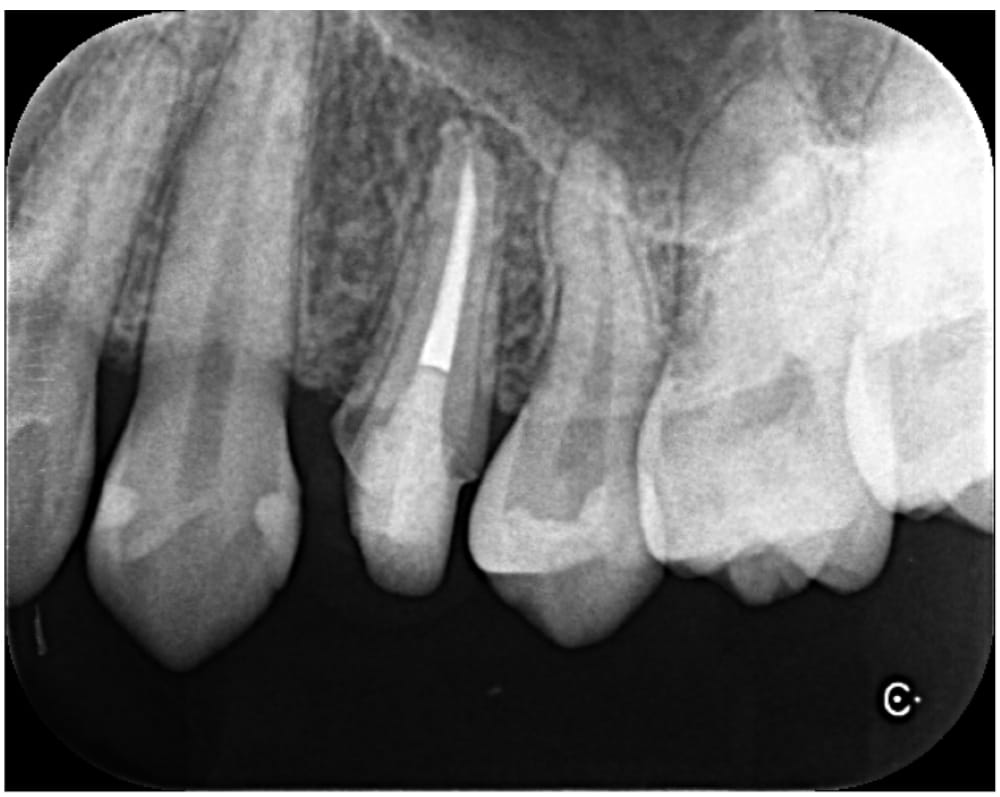

左上の第一小臼歯(4番)には虫歯が認められ、レントゲン・CTにて明瞭な骨吸収像が認められました。痛みなどの症状はないものの、このまま被せ物の治療をやりかえる場合、将来的に根の先の膿が大きくなる可能性があるため、根管治療が第一選択であるとお伝えし、根管治療を開始することになりました。

金属製のスクリューポストが入っていたため、残存歯質に負担がかからないように超音波の振動で除去を行いました。比較的シンプルな根管形態であったため、治療は1回で完了し、ファイバーポストを併用してラバーダム防湿下でコア築造まで行いました。